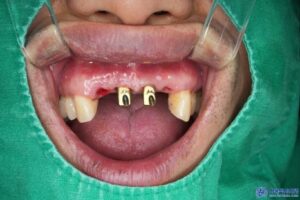

환자분의 기존 보철물과 지대주를 제거하고

보철물 제작을 위한 스캔을 진행하였습니다.

보통 보철물을 제작하게 되면

1~2주일의 시간이 소요됩니다.

하지만 수정구치과 서울박사치과에서는

원내 기공소를 운영하기 때문에

빠른 제작이 가능합니다.